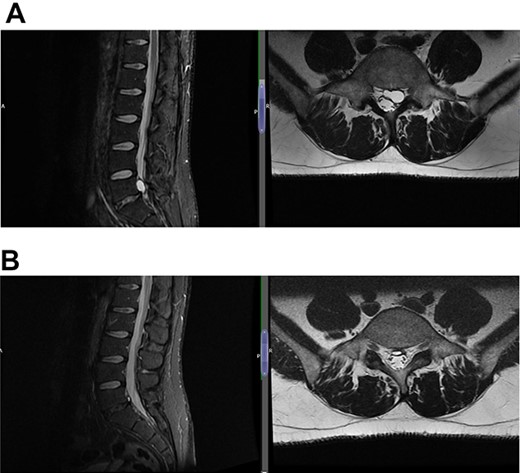

Case 1 L5-S1 level: there is disc desiccation and slight disc height loss; there is disc protrusion (including a cystic component) with impingement to the left traversing S1 nerve root.

(A) Case 2—initial MRI shows a slightly unusual abnormality associated with the L5-S1 compressing the left transiting S1 nerve root and is almost certainly a fragment of extruded/sequestered disc, and (B) case 2—updated MRI shows a significant decrease in the previously seen cystic lesion at L5-S1 level now measuring 4 mm (AP diameter, previously 11 mm).